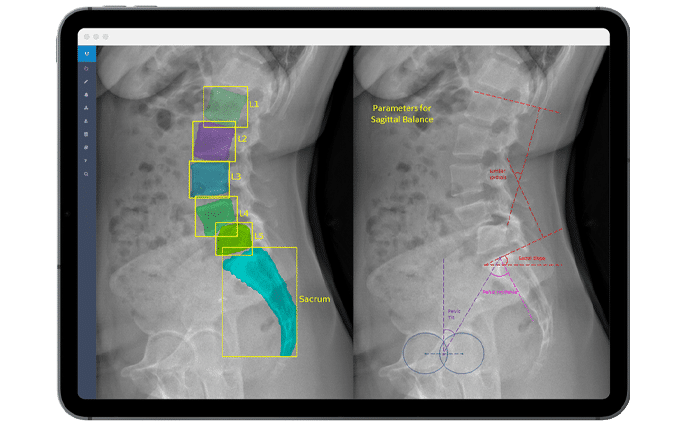

KI-basierte Analyse quantitativer radiologischer Parameter

Wir extrahieren quantitative Bildgebungsendpunkte, Produktleistungskennzahlen (Fusion, Senkung, Ausrichtung) und morphoanatomische Messungen mit Präzision. Unsere KI-gestützten Tools beschleunigen die Analyse um 50 % im Vergleich zu herkömmlichen manuellen Arbeitsabläufen und gewährleisten dabei Genauigkeit und Reproduzierbarkeit.

Bildanalyse der Wirbelsäule für klinische Studien, Register und Forschung.

Wir verfügen über umfassende Erfahrung in der Planung und Durchführung klinischer Studien mit Bildgebungsendpunkten für alle wichtigen Wirbelsäulentherapien, einschließlich Fusion, Bewegungserhaltung und Deformitätskorrektur – von der frühen Machbarkeitsstudie bis zur Post-Market-Überwachung.

Wirbelsäule

Can artificial intelligence support or even replace physicians in measuring sagittal balance? A validation study on preoperative and postoperative full spine images of 170 patients // mehr lesen

Die Functional X-Ray Analysis (FXA) Software unseres Imaging Core Labs analysiert genau und präzise über 150 radiologische Parameter der Wirbelsäule, Hüfte und Knie.